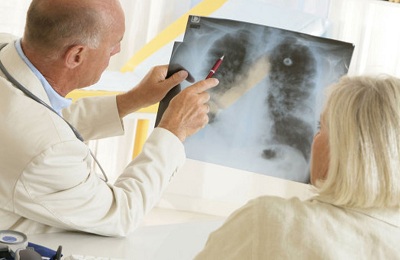

- Рентгенография. Не выявляет очагов специфического (гранулематозного) воспаления легких в виде теней. Возможны усиление легочного рисунка и образование кальцинатов (солевых отложений).

Для постановки диагноза делают общий анализ крови, рентгенографический снимок в прямой и боковых проекциях, проводят исследование мокроты с определением специфических клеток.

- Дети склонны к бронхоадениту (увеличение группы лимфоузлов в области рядом с бронхами), поэтому на рентгенограмме чаще выявляется воспаление в этой области.

Туберкулезная интоксикация в большей степени определяет общую реакцию организма на внедрение микобактерий. Подобный вариант, а также туберкулезное поражение ВГЛУ (внутригрудных лимфатических узлов) и первичный туберкулезный комплекс (ПТК) распространен у детей и подростков. Для постановки диагноза пульмонологам требуются лабораторные исследования, положительная реакция диагностических тестов (проба Манту, диаскинтест), данные осмотра и анамнеза в сочетании с отсутствием специфических изменений в легких по данным флюорографии или рентгенографии.

Особенность данного патологического процесса — отсутствие изменений в легких по данным рентгенологических исследований.

| Рентген, флюорография | Для картины туберкулезной интоксикации характерно отсутствие специфического поражения ткани легкого. |

Туберкулезная интоксикация не диагностируется рентгенологически, для этого делается обзорная рентгенограмма или срединная томограмма.

- Рентгенологическое исследование. Именно по рентгенологическим данным ставится окончательный диагноз при многих формах туберкулеза. Однако первичные формы туберкулеза и небольшие увеличения лимфоузлов часто не просматриваются рентгеном. В этом случае используется метод КТ.